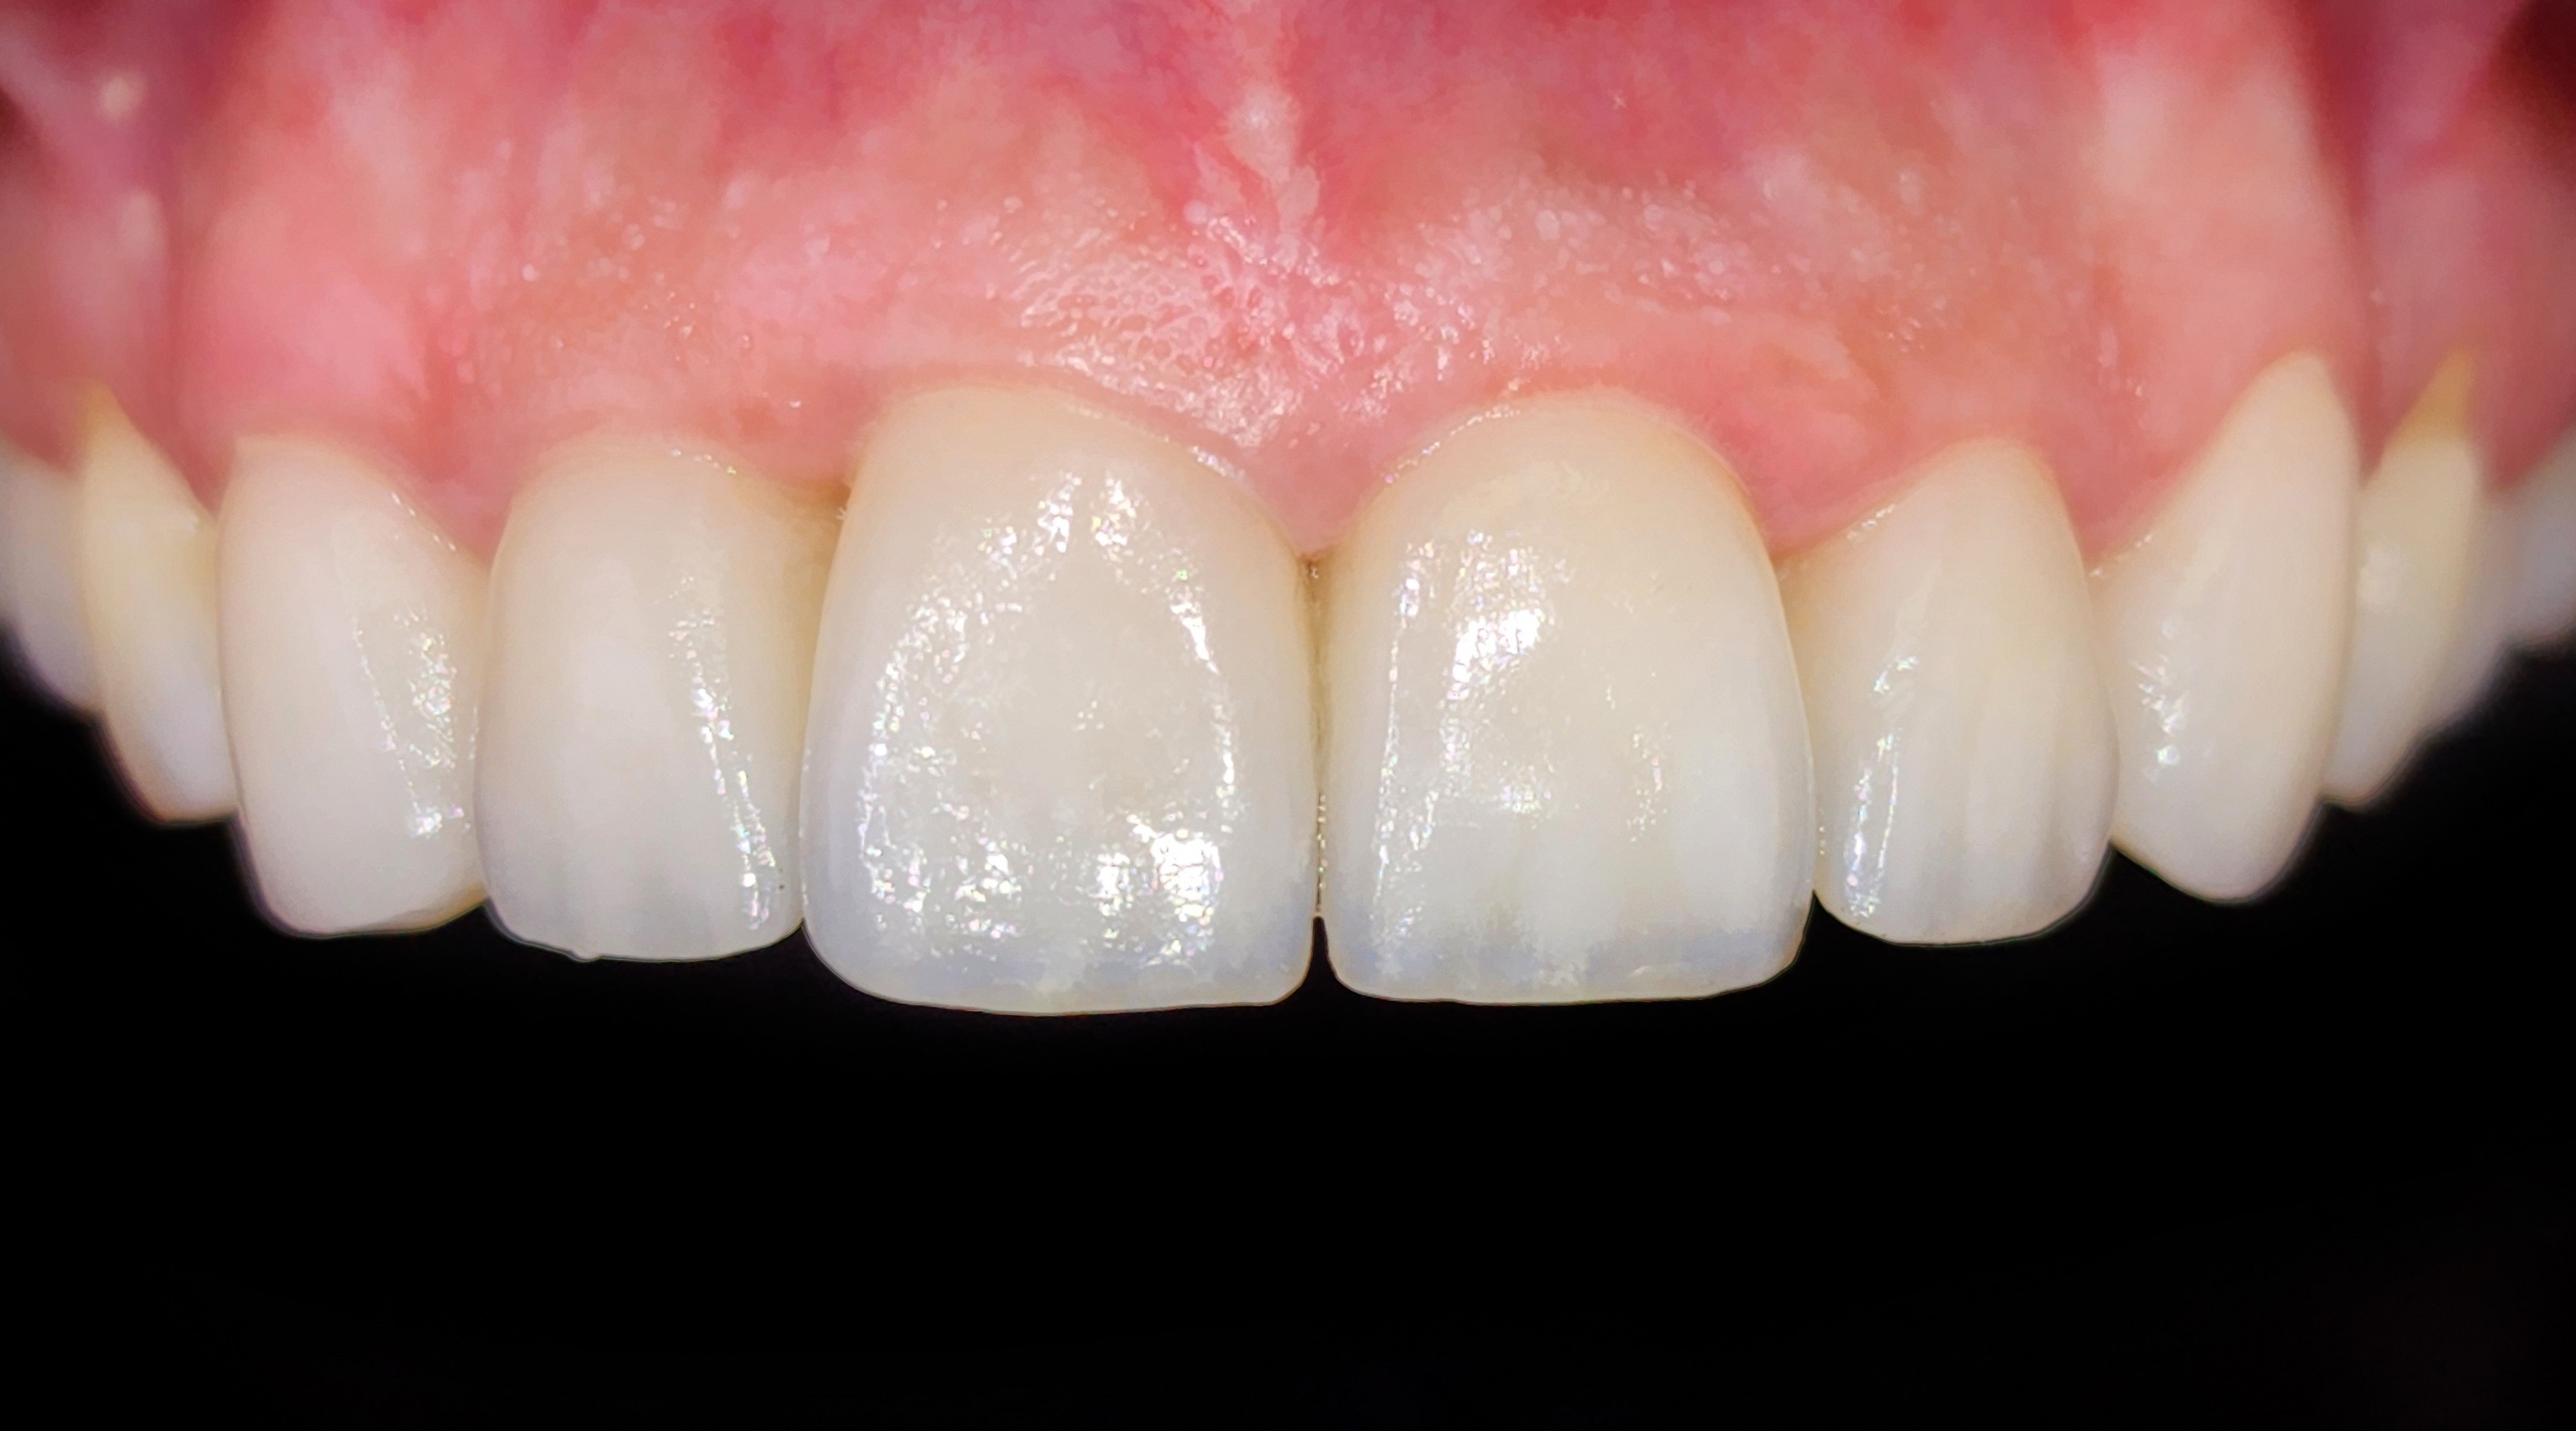

גלריה ציפוי חרסינה לשיניים

מרווח בין שיניים קדמיות